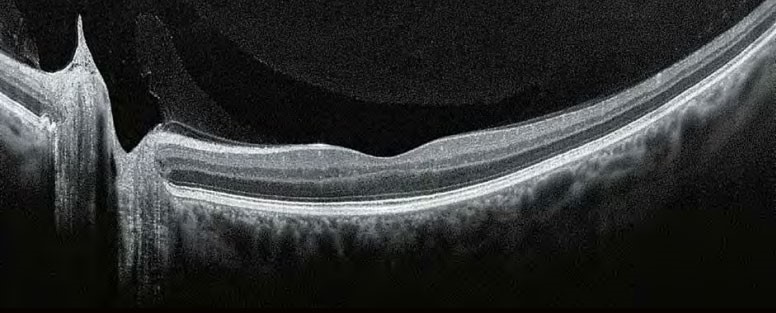

Завдяки визнаній оптиці Canon, Xephilio OCT-A1 пропонує чудову якість зображення. З цифровою розподільчою здатністю до 1.6 мкм система дозволяє чудово диференціювати структури та окремі шари сітківки. Висока швидкість сканування 70,000 A-сканів/сек забезпечує скорочення часу дослідження, зазвичай приблизно до двох секунд, та призводить до зменшення артефактів руху й підвищення комфорту пацієнта.

Xephilio OCT-A пропонує відмінну оптичну розподільну здатність. Усередненням безлічі сканів (до 200)досягається прекрасна якість зображення з дивовижною деталізацією.

За допомогою Xephilio OCT-A1 ви можете усереднити до 200 сканувань, щоб досягти розподільчої здатності зображення, що дозволяє детально бачити як структуру шарів сітківки, так і пошарову структуру скловидного тіла. Для оптимальної візуалізації система пропонує спеціальні режими сканування для скловидного та судинного зображення, а також особливо широку ширину сканування до 13 мм